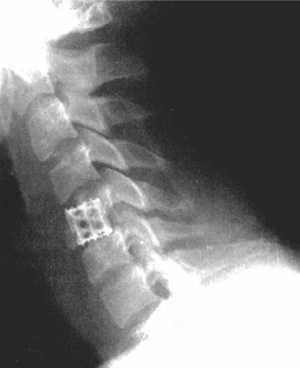

Рис. 3.6. Компрессионный перелом тела

С5 позвонка до и после операции. Стабилизация металлической конструкцией. |